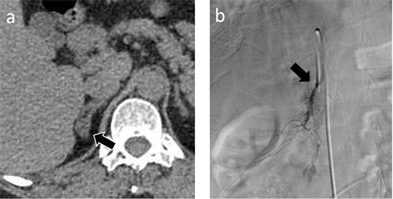

A blood sample from the right adrenal vein (RAV) was also obtained. Cannulation of the right adrenal vein was difficult because of its small diameter, short length, acute angle of entry into the IVC, and anatomic variations. In general, a 5.2-Fr Mikaelsson catheter (Carry; UTM, Aichi, Japan) with one side hole was used, which provides easy blood sampling (Figure 2). When the cannulation was difficult, other catheter types were used (5Fr Cobra Shaped Carry or 4.2Fr RAV Carry; UTM, Aichi, Japan).

Figure 2. 58-year-old woman with primary aldsteronism (patient 43). Endocrinologists evaluated the parameters and determined that only right adrenal gland was involved. This patient underwent adrenalectomy, and histological analysis confirmed the adrenal adenoma. (a) Axial CT image with 1 mm slice thickness demonstrating a low-density nodule in the right adrenal grand (arrow). (b) Venogram of the right adrenal vein. A blood sample was obtained via a 5.2-Fr catheter in the right adrenal vein (arrow).